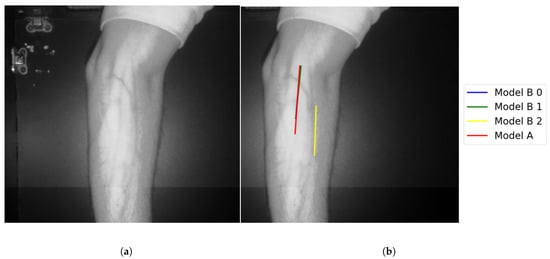

- Identifying veins using both Model A and Model B: Vein selection was marked successfully for 56.5% of all test cases, using both models proposed in the vein selection stage.

- Identifying veins using single model Model A, or Model B: The former model achieves higher accuracy in selecting the veins compared to Model B. Since the former model has theongestine without applying any validation, it outputs directly theongestine detected from theargest perimeter contour. Model B achievesess accuracy performance, 61%. It omits the vein selection when there are noines coincident. The test images where its veins were successfully selected by using Model A are already identified by deploying Model B. In these images, Model B is providing ateast two vein selections. However, these selections do not provideines coincidentally. This explains theow accuracy when deploying Model B in the vein selection stage.